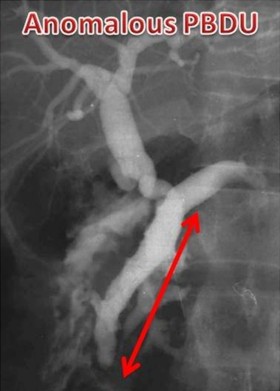

Figure 3. Three ERCP images showing the definition of a short common channel (short CC: channel length 3 mm), a long common channel (long CC: channel length 12 mm) and anomalous pancreaticobiliary ductal union (anomalous pancreaticobiliary ductal union: channel length 4 cm). CC: common channel; PBDU: pancreaticobiliary ductal union |

The reporting of the ERCPs was done in a stepwise fashion. The first step was to identify ERCPs in which both ducts were filled and pancreaticobiliary confluence was clearly identified in more than one image (inclusion criteria for study) (Figure 1). ERCPs in which only one duct (pancreatic or biliary) was filled or the confluence of the pancreatic and bile ducts was not clearly visualized were excluded from the study (Figure 1). Second, in those ERCPs included in the study, we then reported on whether the pancreatic and bile ducts opened into the duodenum separately or if the ducts were joined to each other and a common channel opened into the duodenum(Figure 2). Third, we measured the length of the common channel in the latter (Figure 3). To do so, we measured the actual length of the channel as it appeared on the images and corrected it with a magnification factor, as determined by the actual and imagined (as on images) width of the endoscope [15, 21]. If the corrected length of the united duct was less than 6 mm, it was reported as a short common channel. If the corrected length of the united duct was between 6 and 15 mm, it was reported as a long common channel. If the corrected length of the common channel was more than 15 mm, it was presumed that the ductal union had occurred outside the duodenal wall and such patients were reported as having anomalous pancreaticobiliary ductal union [20, 22]. For patients with anomalous pancreaticobiliary ductal union, we determined the pattern and angle of the ductal union. Anomalous pancreaticobiliary ductal union was reported as P-B type when the pancreatic duct appeared to join the bile duct and B-P type when the bile duct appeared to join the pancreatic duct. The angle of union was the actual angle at which the union occurred between two ducts [23].

The distribution of pancreaticobiliary ductal union in 174 control group patients with no pancreaticobiliary disease was as follows: separate opening in 86 (49.4%), a short common channel in 50 (28.7%), a long common channel in 32 (18.4%) and anomalous pancreaticobiliary ductal union in 6 (3.4%). In contrast to the control group, the distribution of pancreaticobiliary ductal union in the 21 patients with tropical calcific pancreatitis was as follows: separate opening in 5 (23.8%; P=0.036; OR=0.32, 95% CI: 0.11-0.91), a short common channel in 1 (4.8%; P=0.017; OR=0.12, 95% CI: 0.02-0.95), a long common channel in 7 (33.3%; P=0.144; OR=2.22, 95% CI: 0.83-5.94) and anomalous pancreaticobiliary ductal union in 8 (38.1%; P<0.001; OR=17.2, 95% CI: 5.19-57.2) (Table 2). The data suggest that separate openings and a short common channel were less often seen in tropical calcific pancreatitis as compared to the control group and a long common channel and anomalous pancreaticobiliary ductal union were more often seen in tropical calcific pancreatitis patients as compared to the control group. The type of anomalous pancreaticobiliary ductal union in the 2 groups was different: 6 (75.0%) of the 8 patients with tropical calcific pancreatitis had the B-P type of anomalous union in contrast to the control group in whom five (83.3%) of the 6 patients had the P-B type of anomalous union (P=0.103; OR=15.0, 95% CI: 1.03-218). The bile duct had joined the pancreatic duct in the neck region in one, the body region in 4 and the distal body/tail region in one patient (Figure 5). The angle of union of the anomalous pancreaticobiliary ductal union was also significantly different in tropical calcific pancreatitis patients (88.1±36.2°) than in control group (20.0±11.5°) (P<0.001). Patients with tropical calcific pancreatitis had significantly (P<0.001) longer anomalous channels (26.6±12.2 mm) than did those in the control group (19.6±6.1 mm).

Figure 5. Tropical calcific pancreatitis. a. ERCP image showing a grossly dilated pancreatic duct with filling defects in the side branches and a dilated bile duct joining it in the pancreatic neck region (arrow) to form anomalous pancreaticobiliary ductal union of the B-P type. b. ERCP image showing a grossly dilated pancreatic duct with multiple large filling defects and the bile duct joining it in the body region (arrow) to form anomalous pancreaticobiliary ductal union of the B-P type. c. ERCP image showing a grossly dilated pancreatic duct with filling defects in the side branches and the bile duct joining it in the distal body region (arrow) to form a very long anomalous pancreaticobiliary ductal union of the B-P type. |